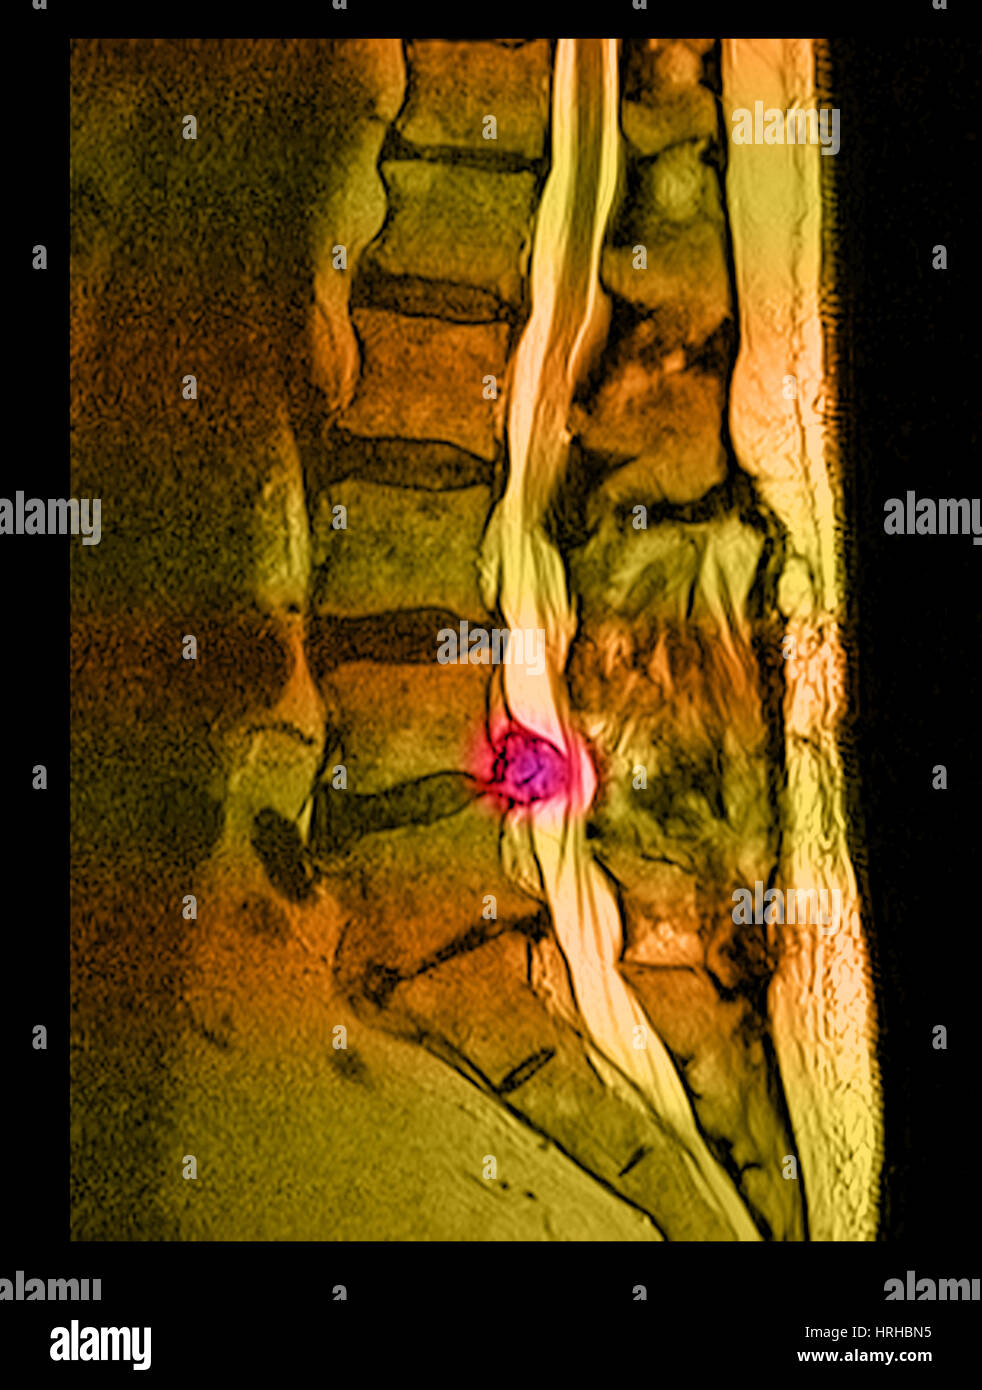

From www.alamy.com

Herniated lumbar disc mri hires stock photography and images Alamy Scoliosis With Herniated Disc   discs rupture and herniate because of degeneration and tears in various parts of the disc.   the patient was diagnosed with lumbar scoliosis combined with lumbar spinal stenosis (lss) and lumbar disc. In addition to low back pain and.   scoliosis is an abnormal lateral curvature of the spine.   painful scoliosis and lumbar disc herniations (ldhs) are well. Scoliosis With Herniated Disc.